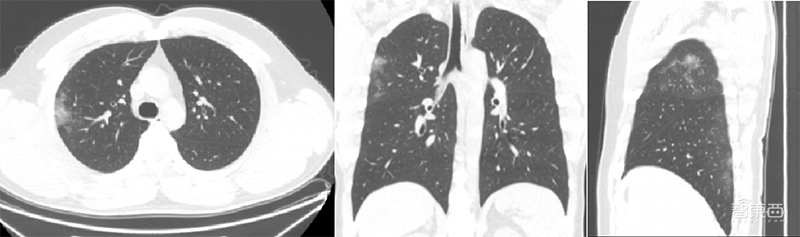

1)图像标准化系统:提供胸部CT图像预处理,确保数据标准化和规范化,辅助提高图像质量。其功能包括:图像裁剪、图像重采样、图像滤波、图像质量恢复、图像标准与归一化。

GE医疗推新冠病毒AI平台!解读背后的硬核技术▲预处理后CT图像(横、冠和矢状面)